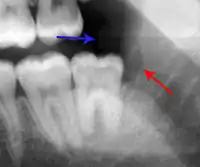

- Radiographs utilized to find dental caries and bone loss laterally or at the apex.

Decay (green) with apical abscess (blue)

Gutta-percha point indicating abscess origin